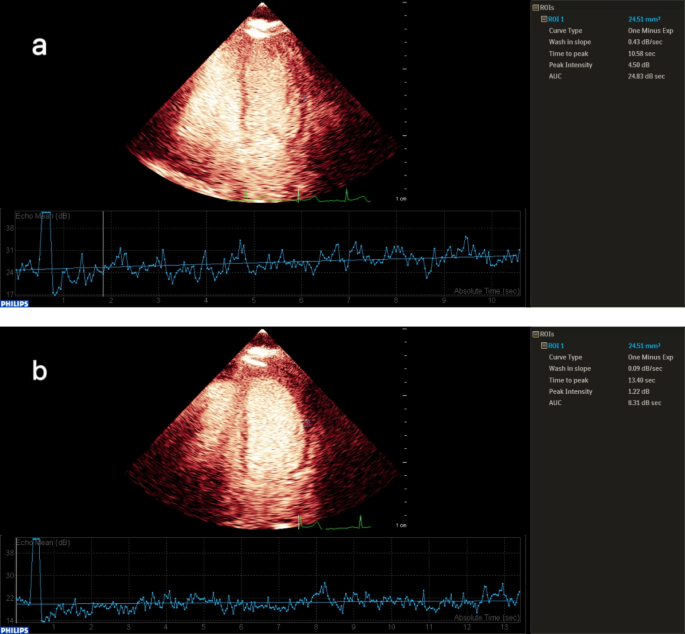

Under both resting and stress conditions, the β values of patients in the INOCA group were significantly different from those in the control group, and the CFR in the INOCA group was significantly different from that in the control group (P < 0.05, Table 2). This indicates that AS-MCE can effectively identify microcirculatory dysfunction in INOCA, demonstrating its superiority in the diagnosis of non-obstructive ischemia (Fig. 1).

Quantitative analysis of contrast echocardiography of the left ventricular lateral wall in the INOCA group: After the drug load test (b), the contrast agent filling rate was significantly slower (Wash-in Slope 0.09 dB/s) compared to before the test (a), the time to peak was delayed (TTP 13.40 s), the peak intensity was reduced (Peak Intensity 1.27 dB), and the total contrast agent flow was significantly decreased (AUC 8.3 dB·s). This perfusion pattern (One Minus Exp curve) highly suggests that there is myocardial blood flow perfusion impairment in this area, and the possible cause may be microcirculation dysfunction. (a) Myocardial perfusion time-intensity curve of the left ventricular lateral wall in INOCA patients before drug stress test. (b) Myocardial perfusion time-intensity curve of the left ventricular lateral wall in INOCA patients after drug stress test.